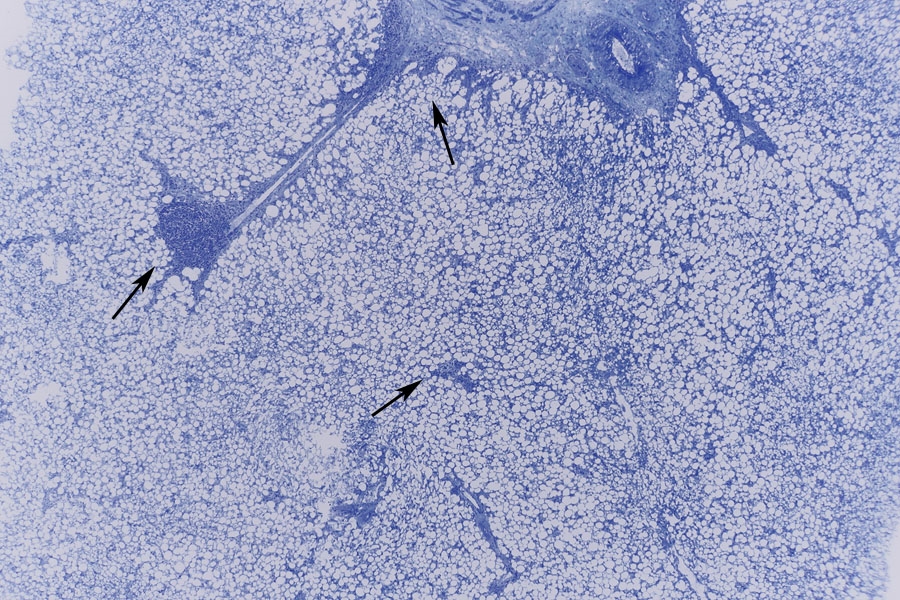

(die Pfeile zeigen auf entzündliche Infiltrate einer Fettleber)

Was in dem ersten Bild zu sehen ist, ist eine maximal verfettete Leber, eine so genannte Fettleber oder auch steatosis hepatis. Die ist beim Menschen oft durch Alkohol bedingt, kann aber auch durch die übermäßige Zufuhr anderer Kalorien oder einen gestörten Fettstoffwechsel bei Diabetes mellitus bedingt sein. Die Fettleber ist in der überwiegenden Zahl der Fälle reversibel, so dass ich denke dass auch unsere Gans überlebt hätte wenn sie nicht den Kopf verloren hätte. Doch frage ich mich was die Gans mit ihrem Ammoniak macht.

gemacht. Damals war die Leber aber nicht so weit verfettet wie jetzt. Auch in diesem Präparat waren mir zahlreiche entzündliche Infiltrate aufgefallen (Pfeile). Liegt also eine Fettleberhepatitis vor? Einen narbigen Unbau konnten wir aber wegen des kurzen Gänselebens nicht sehen.